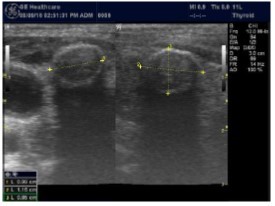

Parathyroid Glands Pathology:

In our study many patients were found to have nodules look very much like PT adenoma, Figure 7 below. At least, 4 patients were subsequently confirmed to have parathyroid adenomas, Figure 8 and 2 patients underwent surgery

Despite the fact that nodular pathology was found to be very prevalent among our study population, it has been found difficult to differentiate between thyroid and parathyroid pathology using ultrasound alone. However, some characteristics of the parathyroid glands might suggest parathyroid pathology in the context of the clinical picture of secondary or tertiary hyperparathyroidism which is very prevalent in ESKD patients’ populations.

Figure 7.Thyroid nodule suspicious for Parathyroid adenoma due to its location

Thyroid nodule suspicious for Parathyroid adenoma due to its location

Figure 8.Nodule that proven to be a parathyroid adenoma, volume =5265 mm3

Nodule that proven to be a parathyroid adenoma, volume =5265 mm3

There are 4 parathyroid glands (2 superior, 2 inferior) imbedded within the thyroid gland. The parathyroid glands are bean-like shape and small (20-40 mg) 25. Sonographically, the parathyroid glands have the following features 25:

Normal glands: indistinguishable from thyroid parenchyma.

Hyperplastic glands: hypoechoic, volume <500 mm3.

Nodular glands: hypoechoic. Volume >500 mm3

Histologically, if the excised gland has volume <500 mm3 it is said to be hyperplastic and if the volume is more than 500 mm3 it is nodular hyperplasia in 80% of cases26. In secondary HPT, the increase in the volume of parathyroid glands is associated with increase in vascularity, as evident in Color Doppler imaging 27.